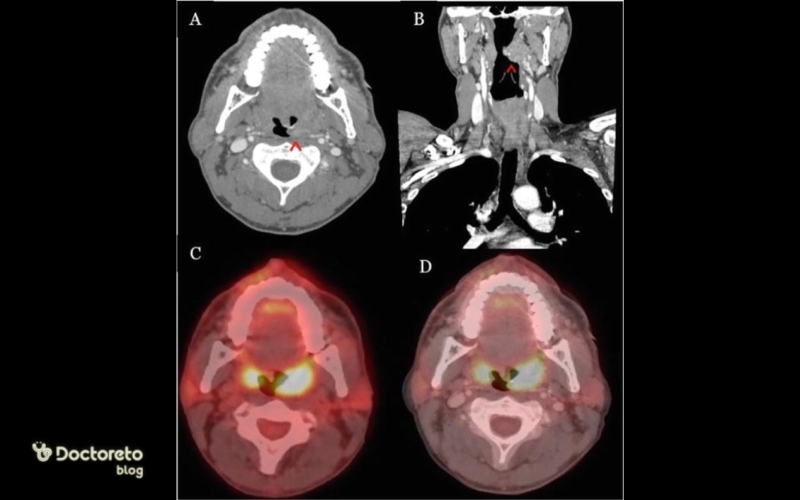

تصویربرداری از سرطان لوزه

تشخیص نهایی سرطان لوزه فقط با عکس ظاهری انجام نمیشود؛ بلکه تصویربرداری پزشکی نقش اصلی را دارد. CT scan، MRI و PET scan رایجترین روشها هستند. این تصاویر به پزشک کمک میکنند میزان درگیری بافت و گسترش احتمالی به غدد لنفاوی یا بافتهای اطراف را بررسی کند.

در مقایسه با عکسهای ساده دهانی، تصویربرداریهای پزشکی نمای بسیار دقیقتری از عمق و وسعت بیماری نشان میدهند. برای مثال PET scan برای شناسایی گسترش تومور مفید است اما برای تعیین بدخیمی سلولها باید بیوپسی انجام شود. به دلیل همین دقت بالا، پزشکان هیچوقت تنها به عکس ظاهری اکتفا نمیکنند. تصویربرداری برای تعیین مرحله سرطان نیز ضروری است و میتواند مسیر درمان را کاملاً تغییر دهد.